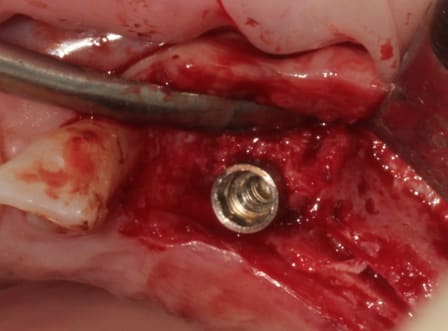

et un et deux et trois

D1 pour "assouplir"

éponge

implant lisse conique

éponge...